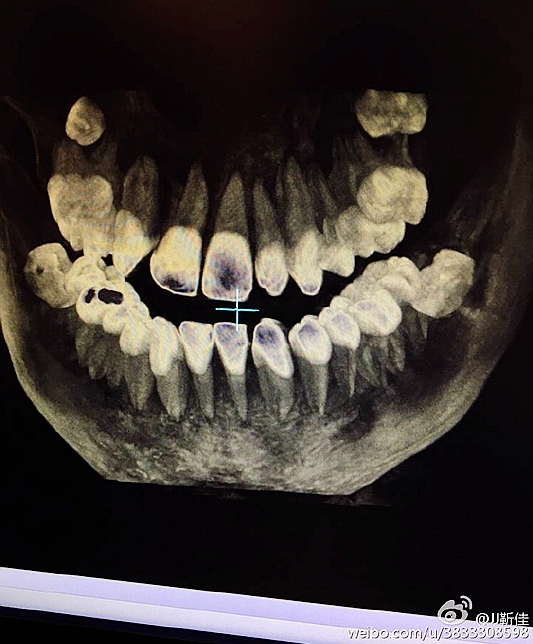

2016.8.3涉縣美康口腔王主任種植牙于額外牙拔除

左下67缺失

ct定位

術(shù)后拍片